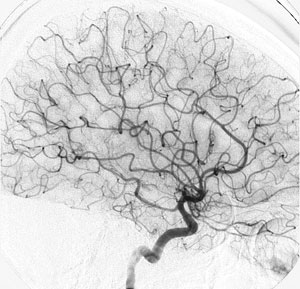

CASO 4 : Radiocirugía como tratamiento único en malformación arteriovenosa de mediano volumen en paciente joven con crisis convulsivas

IAngiografía al momento de la radiocirugía

Angiografía al año y medio después de la radiocirugía que muestra la curación de la paciente sin ningún efecto adverso ni secuelas.